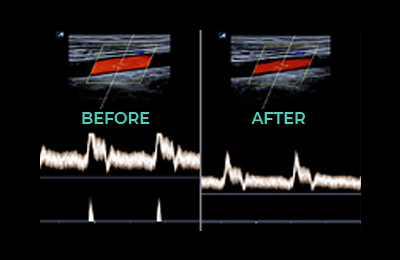

L3-12H

High density linear transducer (3-12MHz)

Application:

Breast, EM, MSK, Vascular, Small Parts